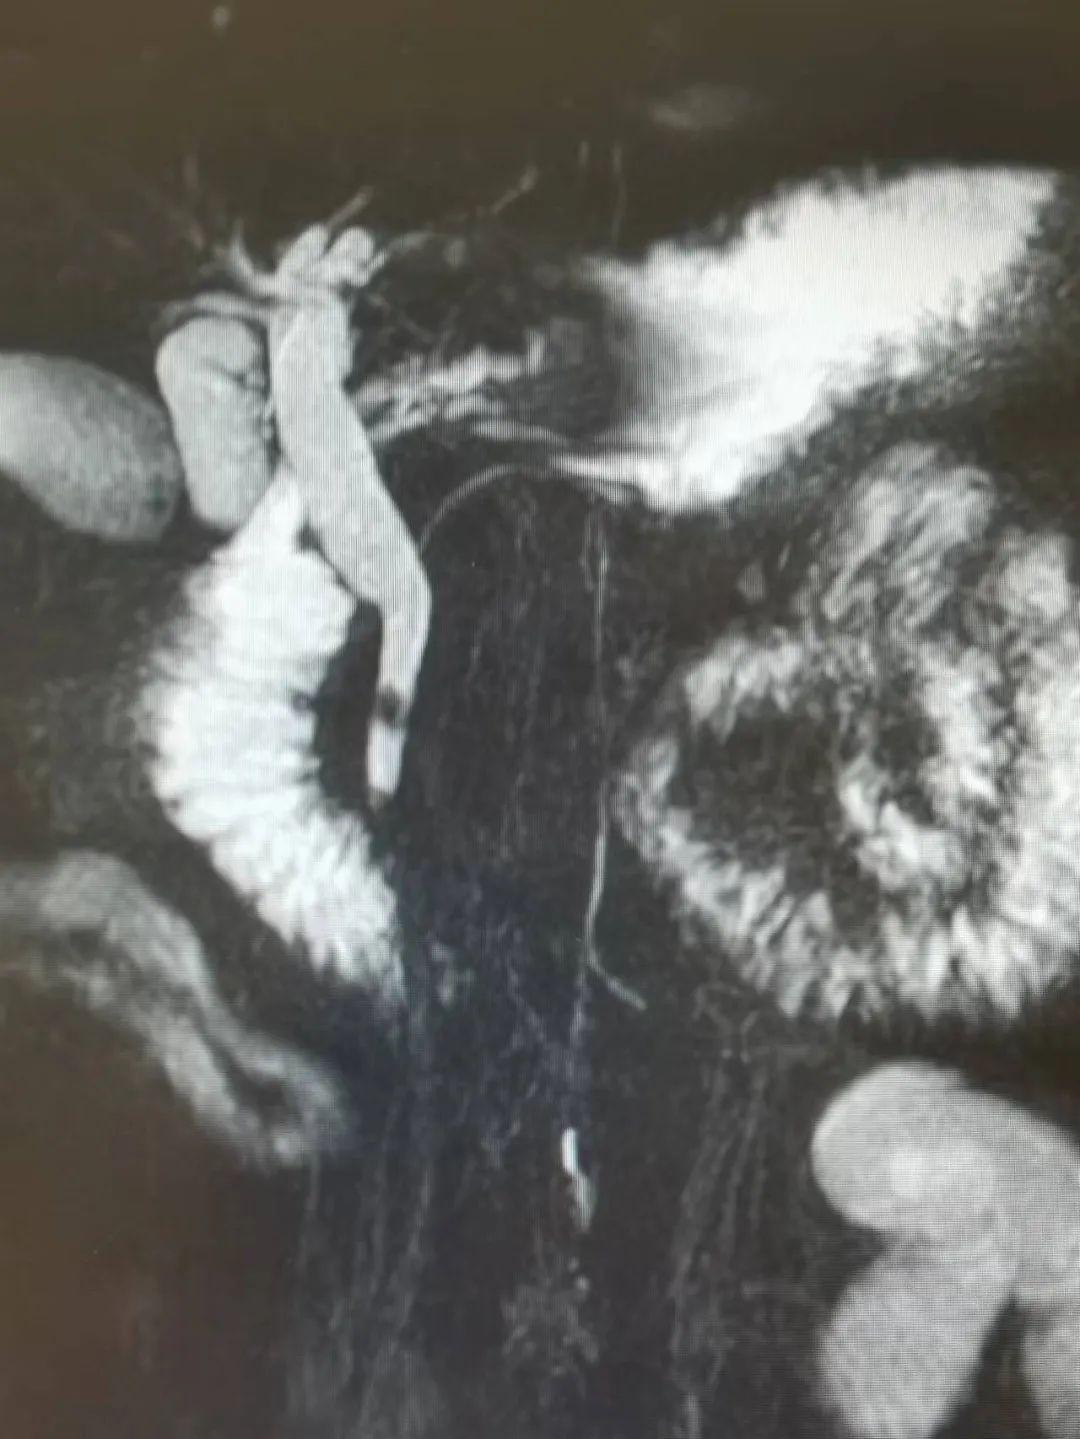

患者术前检查发现,胆囊颈管直径约0.6cm,胆总管直径为0.8cm-1.0cm,提示胆道镜置入困难;加之患者两年前曾因急性胃穿孔在当地医院接受过“胃大部分切除”术,可能存在严重的腹腔粘连及解剖变异。这些因素都给手术增加了难度,杨涛主任带领团队提前做好各项应对预案。

来自卢龙县的李先生今年57岁,因“剧烈腹痛 胆囊结石 胆道梗阻 急性胆管炎”入院。经过病例讨论,秦皇岛市第一医院普通外科一病区为其制定“腹腔镜、胆道镜两镜联合,经胆囊颈管置入网篮至胆总管内取石”的治疗方案。